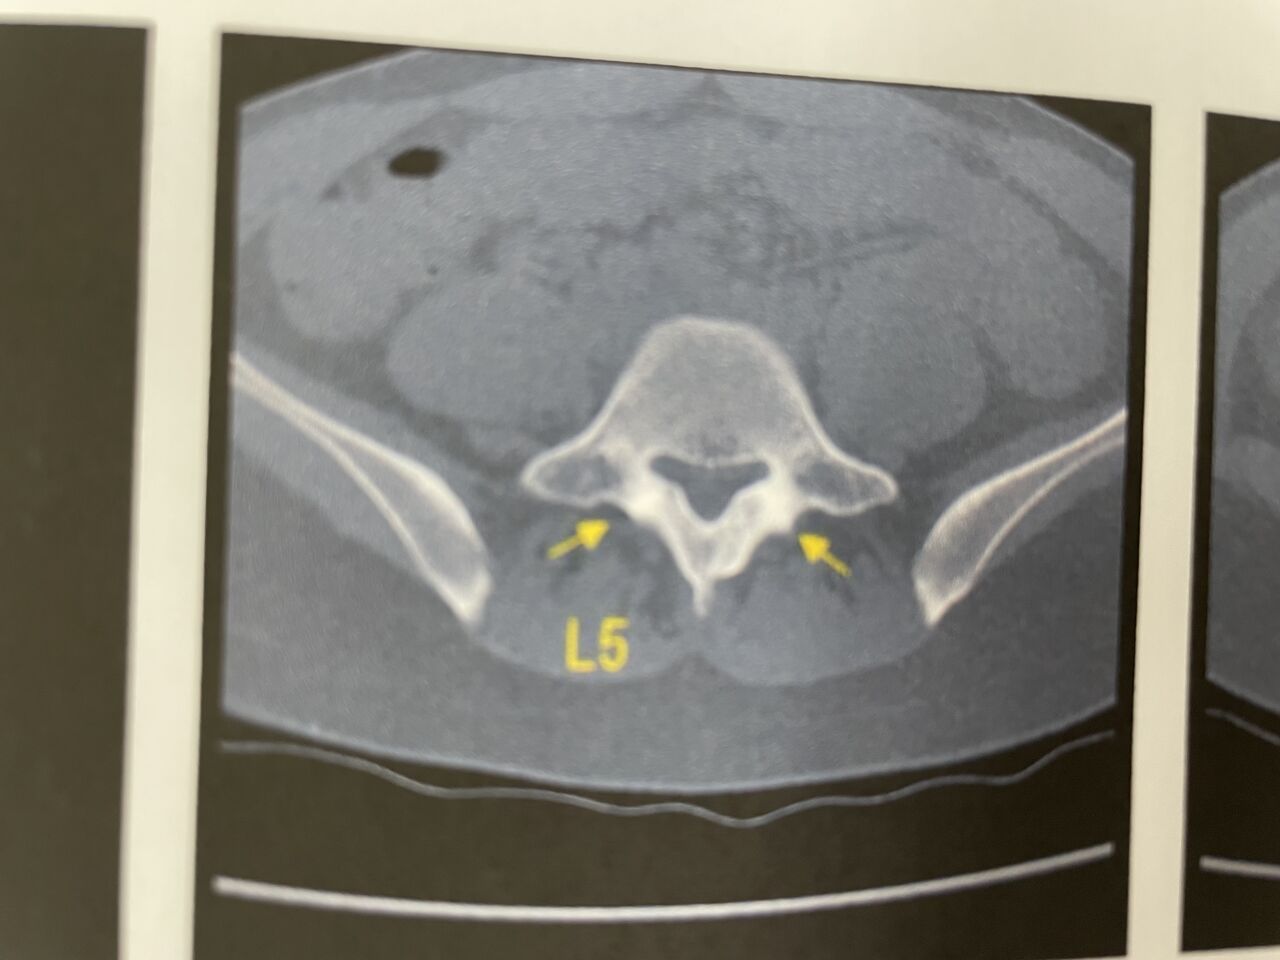

高校県大会 バレーボール出場選手

体幹トレーニング、ストレッチ、テーピングにて、

疲労骨折あるも、

顧問先生と連携取り、1週間後の試合に出場予定